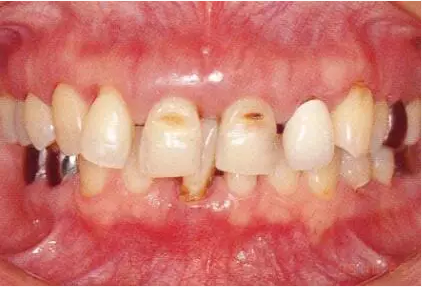

2222222222.png

▲圖19-1

40歲,女性。來院主訴為牙齦出血,牙體晃動?;颊卟晃鼰?,因此沒有全身性問題。有明顯的牙周炎,發(fā)生了牙體移動,前牙區(qū)前突。下頜右側(cè)磨牙缺失,醫(yī)生認為有必要進行包括牙周修復(fù)、正畸治療、種植治療等在內(nèi)的綜合性治療。